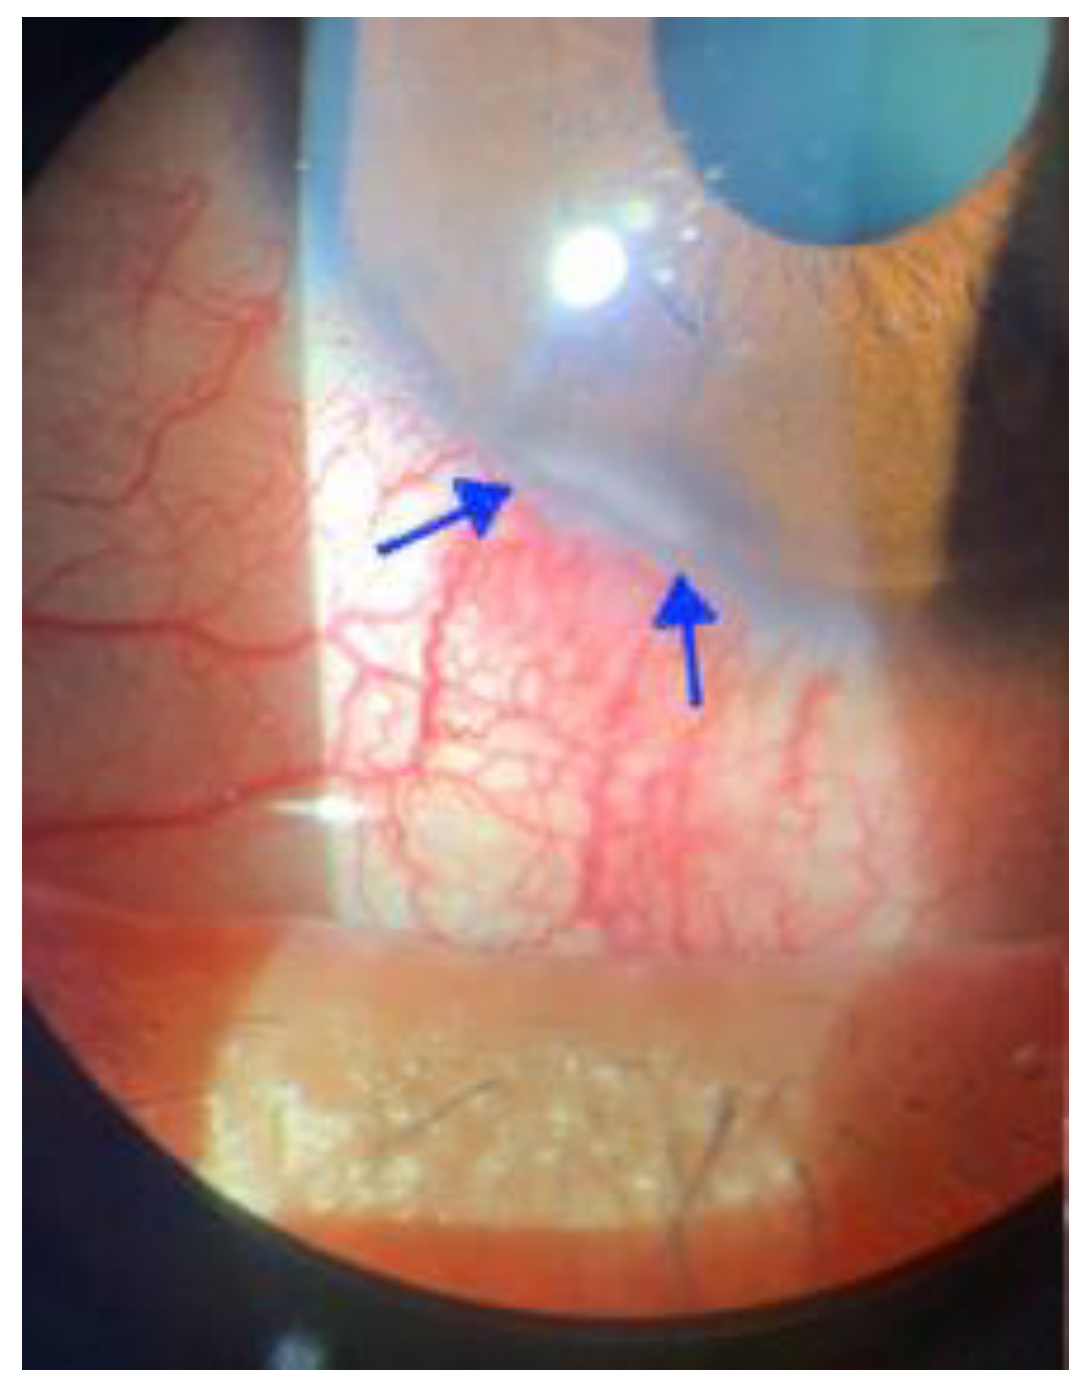

- Foos, W.; Wroblewski, K.; Ittoop, S. Subconjunctival nodule in a patient with acute monkeypox. JAMA Ophthalmol. 2022, 140, e223742. [Google Scholar] [CrossRef] [PubMed]